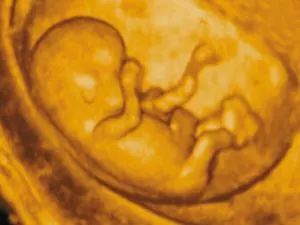

现在一般大排畸检查的彩超以四维彩超为主,三维彩超和四维彩超的区别主要在于在一个“时间维”,也就是说,三维彩超是图片,是静态的,四维彩超是录像,是动态的,可以让孕妈妈看到胎儿一连串的动作,所以四维看起来会更清楚明了,三维彩超只能是某个时间点上的照片,四维彩超的就可以做成DV那样连续的,可以刻录光盘。三维彩超和高清四维彩超一样的有排畸的作用,高清四维彩超更加精确。 三维彩超侧重观察五脏六腑是否畸形,排除结构畸形。四维彩超还观察运动神经系统是否正常,运动是否协调。

彩超其实还是黑白的,而三维、四维彩超在做出三维、四维图像的时候才可能是土黄色,也并非彩超就是彩色的。被称为彩超,是因为会用彩色标注心脏、血流等指标。

三维彩超、四维彩超的图像则是后期生成的,并不是说观察到的图像就是三维、四维的,而是仍然用普通彩超观察,然后通过仪器中的转换软件将观察到的平面图像转成三维、四维的立体图像,说得更直白一点,如果将你的家用电脑中装上类似软件,你就可以把普通B超的图像自己在家里转换成立体的了。

在诊断的意义上,三维彩超、四维彩超几乎是一样的,没有任何对诊断哪一种更有利的说法,只不过是不懂得B超图像的人也能看出模样而已。它们的意义也就在于,您能看见宝宝在肚子里的模样了。

三维彩超和四维彩超的最佳时间是22-28周,而这段时期检查,因为胎儿较小,羊水较多,胎儿活动度大,体表也比较丰满,有利于胎儿四维超声成像和胎儿畸形筛查,是排畸的最好时期。